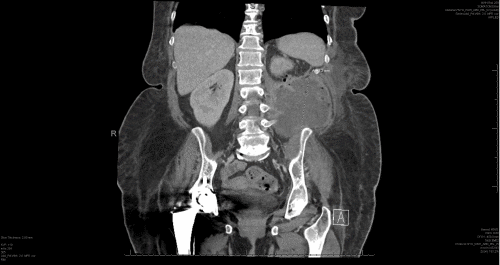

A 62-year-old female who smokes tobacco, with a history of asthma and pyelonephritis, failed outpatient empiric antibiotic treatment and was admitted for sepsis secondary to pyelonephritis with staghorn calculi, severe left hydronephrosis, and a left-sided retroperitoneal abscess (Figure 1).

Figure 1. CT Images at Admission. Published with Permission

A) Coronal view showing loculated fluid collection/abscess containing air bubbles and air-fluid level in the left retroperitoneum, measuring 10.0 × 9.5 × 9.8 cm, extending along the left psoas muscle and beyond the abdominal musculature into the soft tissues of the left flank

B) Large 3.3 cm staghorn calculus in the left kidney, resulting in severe left hydronephrosis and likely calyceal rupture

C) Coronal view on the left showing the connection between the descending colon and left kidney (arrow) and the same pathology shown on the axial view on the left indicated by crossmarker.